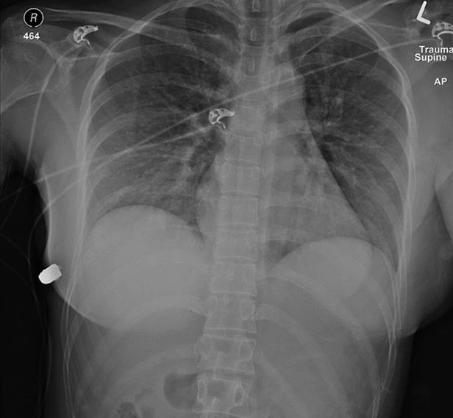

据报道,*弹子**被这名女子的左胸植入物挡开偏离心脏,落入了右胸。她的两个种植体都已被移除,肋骨虽然骨折,所幸无其他大碍,经过治疗她很快就可以康复了。

“病人说她走在街上,突然感觉左胸疼痛发热,低头就看到了血。” 整形外科医生吉安卡洛·麦克伊文纽(Giancarlo McEvenue)的研究小组在《整形外科医生案例研究报告》中这样解释道。目前,对其开枪的凶手仍然不明,至今涉案枪支也未找到。